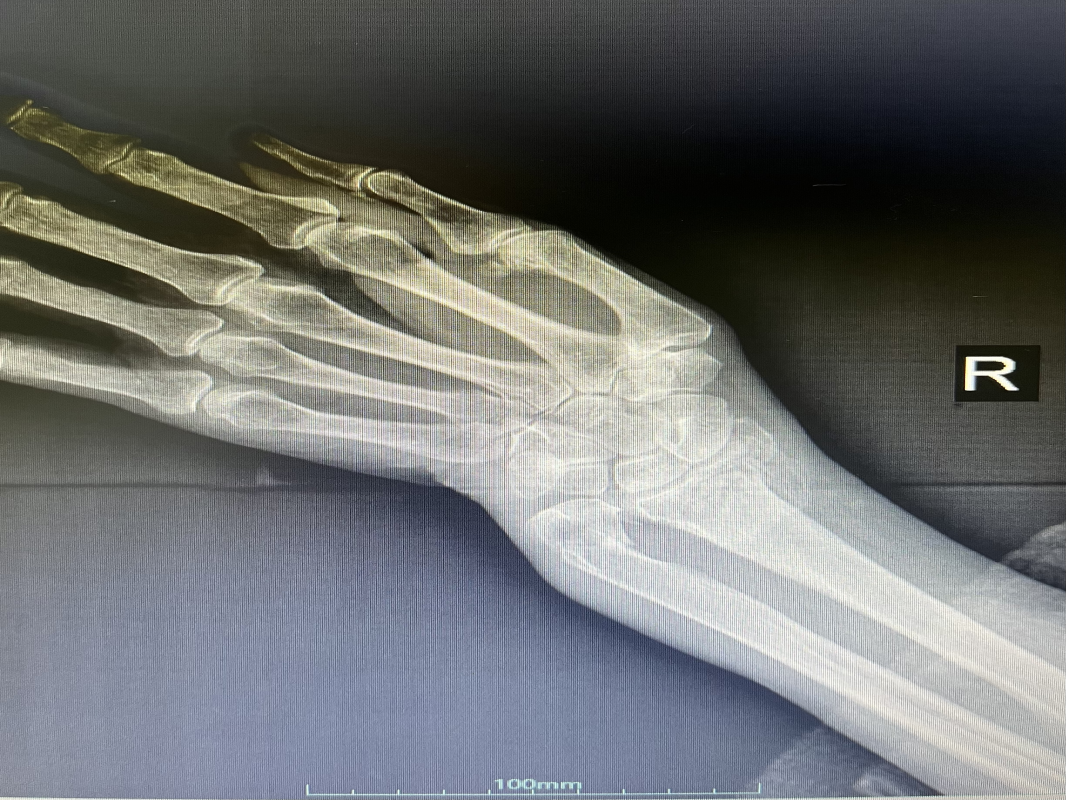

近日,我科收住一位高齡患者,孫某某,女,82歲,患者2小時(shí)前因摔傷致全身多處腫痛、伴活動(dòng)受限。入院后診斷:1.右股骨粗隆間粉碎性骨折;2.右尺橈骨遠(yuǎn)端粉碎性骨折;3.右鎖骨骨骨折;4.右肱骨大結(jié)節(jié)骨折;5.右恥骨下肢骨折;6.重度骨質(zhì)疏松。 鑒于患者屬高齡,損傷重,病情復(fù)雜,入科后科主任魏國(guó)華帶領(lǐng)關(guān)節(jié)骨科醫(yī)護(hù)團(tuán)隊(duì)積極完善相關(guān)檢查、科學(xué)制定治療方案,充分發(fā)揮中醫(yī)骨傷的治療優(yōu)勢(shì),保守與手術(shù)相結(jié)合,對(duì)右尺橈骨遠(yuǎn)端粉碎性骨折行手法復(fù)位石膏托外固定術(shù)。 排除手術(shù)禁忌后,在腰硬聯(lián)合麻醉下行右股骨粗隆間粉碎性骨折閉合復(fù)位PFNA內(nèi)固定術(shù),其余疾病行保守治療,術(shù)后經(jīng)活血化瘀、益氣養(yǎng)血等積極對(duì)癥治療,患者肢體功能恢復(fù)良好,已康復(fù)出院。 股骨粗隆間骨折是老年人常見(jiàn)損傷,俗稱人生最后一次骨折。老年人骨質(zhì)疏松,肢體不靈活,當(dāng)下肢突然扭轉(zhuǎn)、跌倒或使大粗隆直接觸地?fù)p傷,甚易造成骨折。由于粗隆部受到內(nèi)翻及向前成角的復(fù)合應(yīng)力,引起髖內(nèi)翻畸形和以小粗隆支點(diǎn)的嵌壓形成小粗隆蝶形骨折。亦可由髂腰肌突然收縮造成小粗隆撕脫骨折。粗隆部骨質(zhì)疏松脆,故骨折常為粉碎型。 就診地址:酒泉市中醫(yī)醫(yī)院關(guān)節(jié)骨科?? ?? 門診部:二樓205診室 住院部:綜合樓6樓住院部